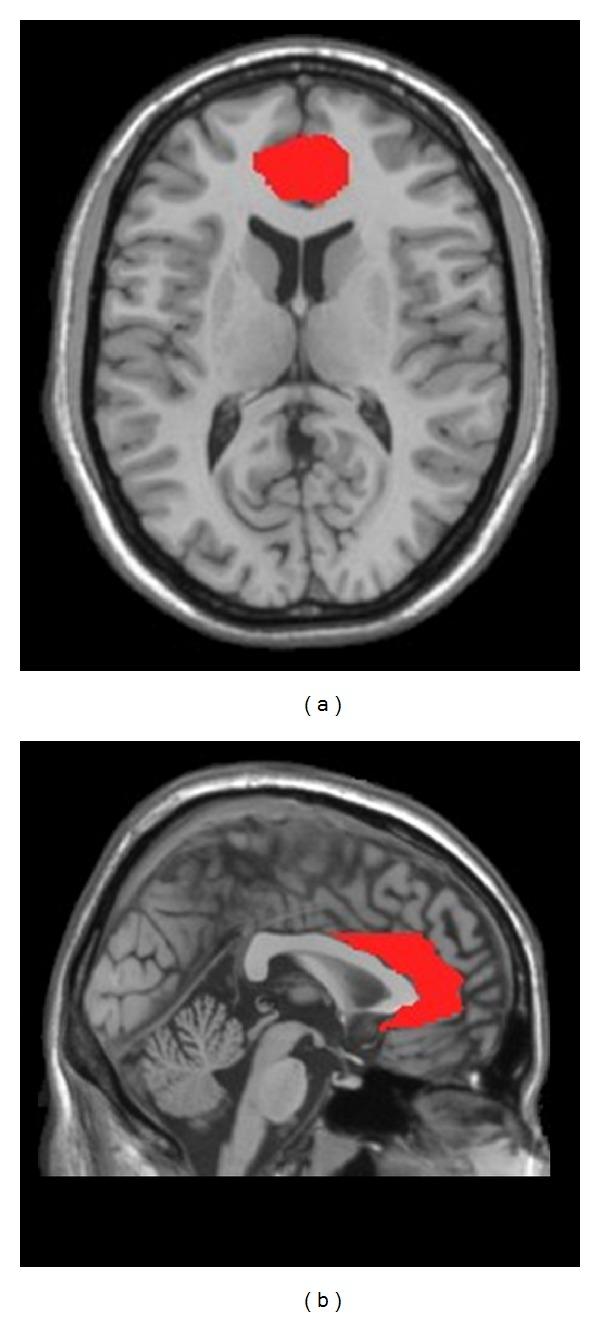

26 PSD patients, 24 stroke patients without depression, and 24 age-matched normal controls underwent the resting-state functional MRI (fMRI) scanning. The bilateral anterior cingulated cortices (ACCs) were selected as regions of interest (ROIs). FC was calculated and compared among the three groups. The association between FC and Hamilton Depression Rate Scale (HDRS) scores of PSD group was investigated.

The FC of the AN was disrupted in PSD patients compared to stroke patients without depression and normal controls. Moreover, the left orbital part of inferior frontal gyrus which indicated altered FC was significantly correlated with HDRS scores in PSD patients.

26例PSD患者、24例无抑郁症的中风患者和24例年龄匹配的正常对照者接受静息态功能磁共振成像(fMRI)扫描。选择双侧前扣带回皮质(ACC)作为感兴趣区(ROI)。计算并比较三组之间的FC。研究PSD组FC与汉密尔顿抑郁量表(HDRS)评分之间的关联。

与无抑郁症的中风患者和正常对照相比,PSD患者的AN的FC受到破坏。此外,显示FC改变的左侧额下回眶部与PSD患者的HDRS评分显著相关。